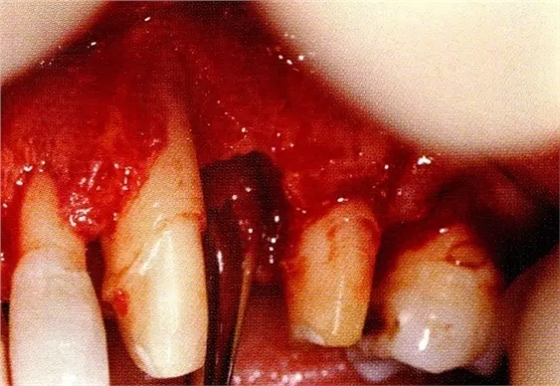

▲圖8-3進(jìn)行全厚瓣翻瓣,將根表面的沉積物、骨缺損的肉芽組織徹底清除,確認(rèn)牙槽骨形態(tài),可看到從頰側(cè)到遠(yuǎn)中存在垂直性和水平性的骨缺損。

▲圖8-4,5為了確保足夠空間實(shí)現(xiàn)更好的再生,使用了2張鈦強(qiáng)化型gore-tex膜。